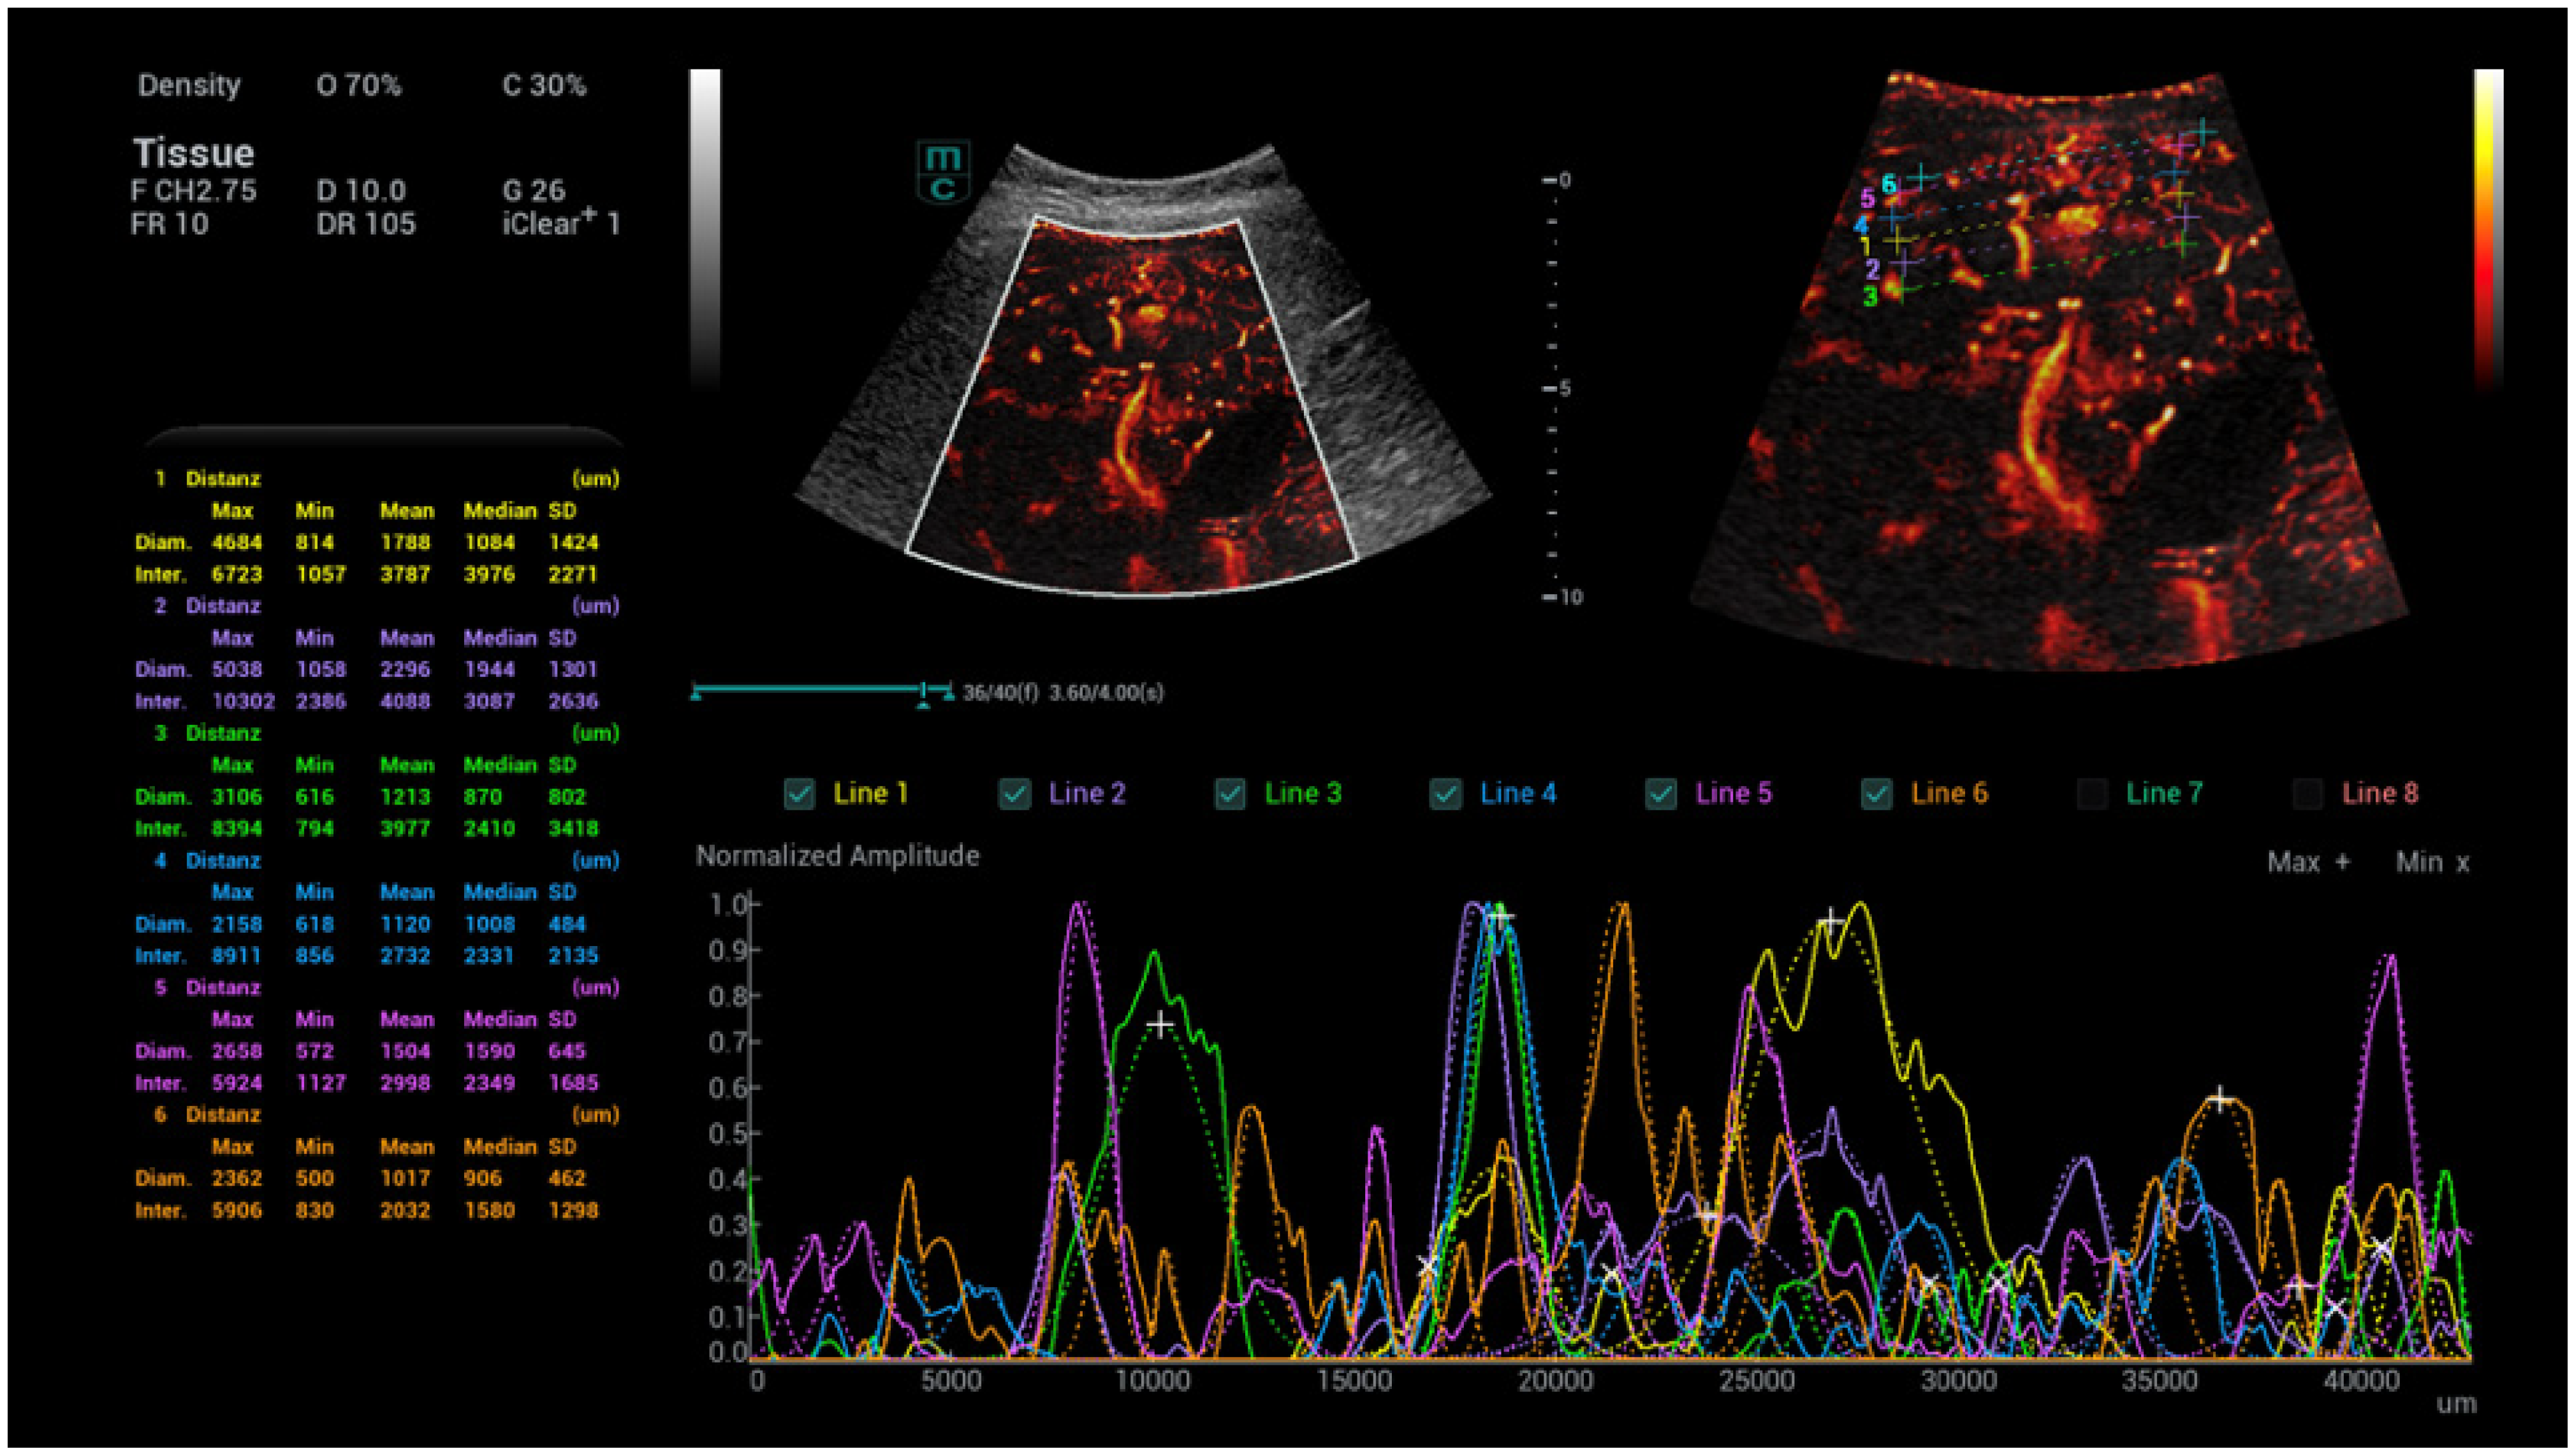

- Kaiser, U.; Vehling-Kaiser, U.; Kück, F.; Gilanschah, M.; Jung, F.; Jung, E.M. Super-Resolution contrast-enhanced ultrasound examination down to the microvasculature enables quantitative analysis of liver lesions: First Results. Life 2025, 15, 991. [Google Scholar] [CrossRef]